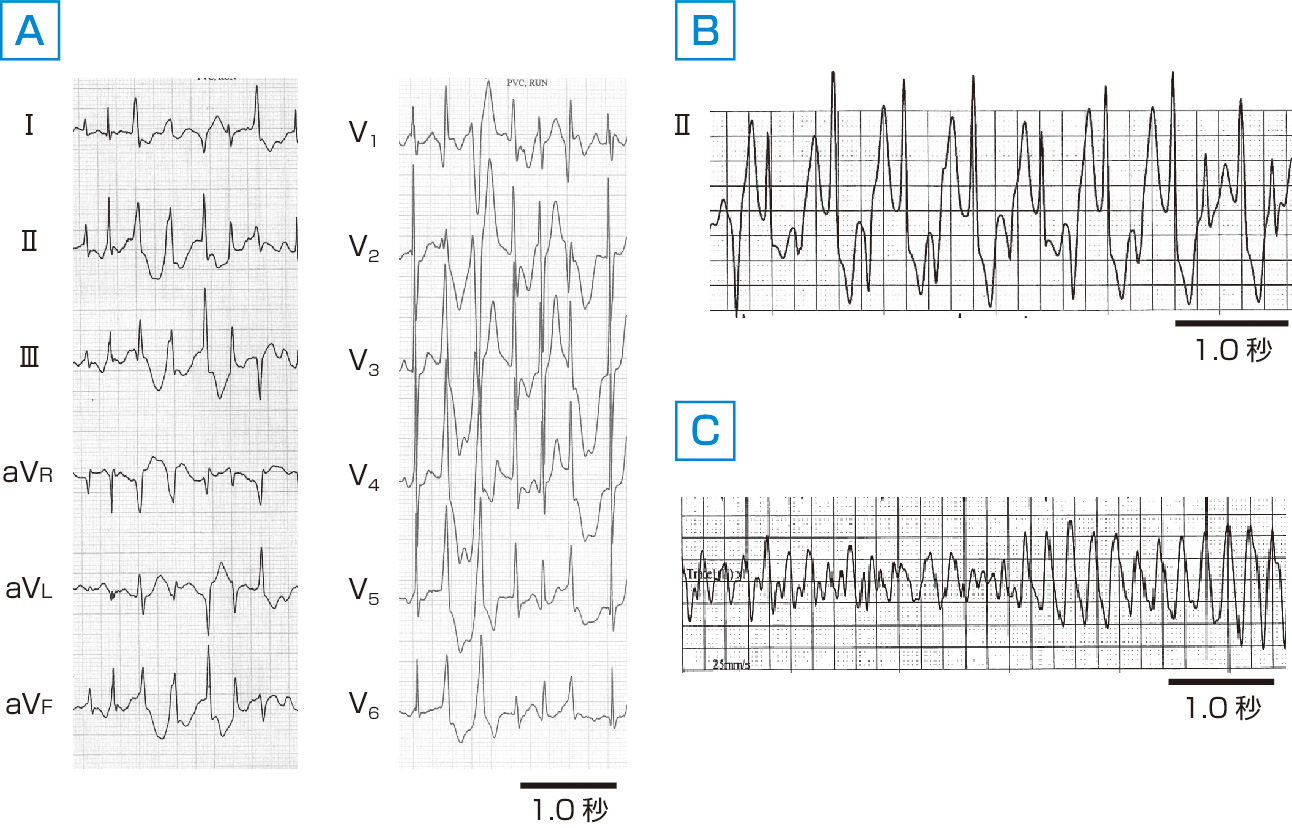

図1 特発性心室頻拍の代表例. A:特発性右室流出路起源心室頻拍.右室流出路付近を起源とする特発性心室頻拍で,心電図では左脚ブロック型の下方軸偏位を示す.多くは非持続性を呈し,撃発活動が発生機序と考えられる.同一起源の心室期外収縮と混在するため,心室期外収縮の延長線上にある心室頻拍ととらえてよい. B:特発性ベラパミル感受性心室頻拍.左室の左脚後枝 (まれに前枝) に関連して発生するリエントリー性心室頻拍であり,持続性単形性を示す.その停止にはベラパミル静注がきわめて有効であり,リエントリー回路の伝導遅延部位がカルシウムチャネルによって脱分極していると考えられる.比較的狭い右脚ブロック型のQRS幅を呈し,後枝起源では上方軸,前枝起源では下方軸偏位となる.

図2 カテコールアミン誘発性多形性心室頻拍. A:運動負荷中に認められた心室頻拍.数種類のQRSが観察される. B:Aの後に認められた2方向性心室頻拍.2種類のQRSが交互に出現する特徴的な心室頻拍である. C:2方向性心室頻拍後に発生した心室細動.カテコールアミン誘発性多形性心室頻拍はこのような心室細動により突然死に至る危険性が高い.